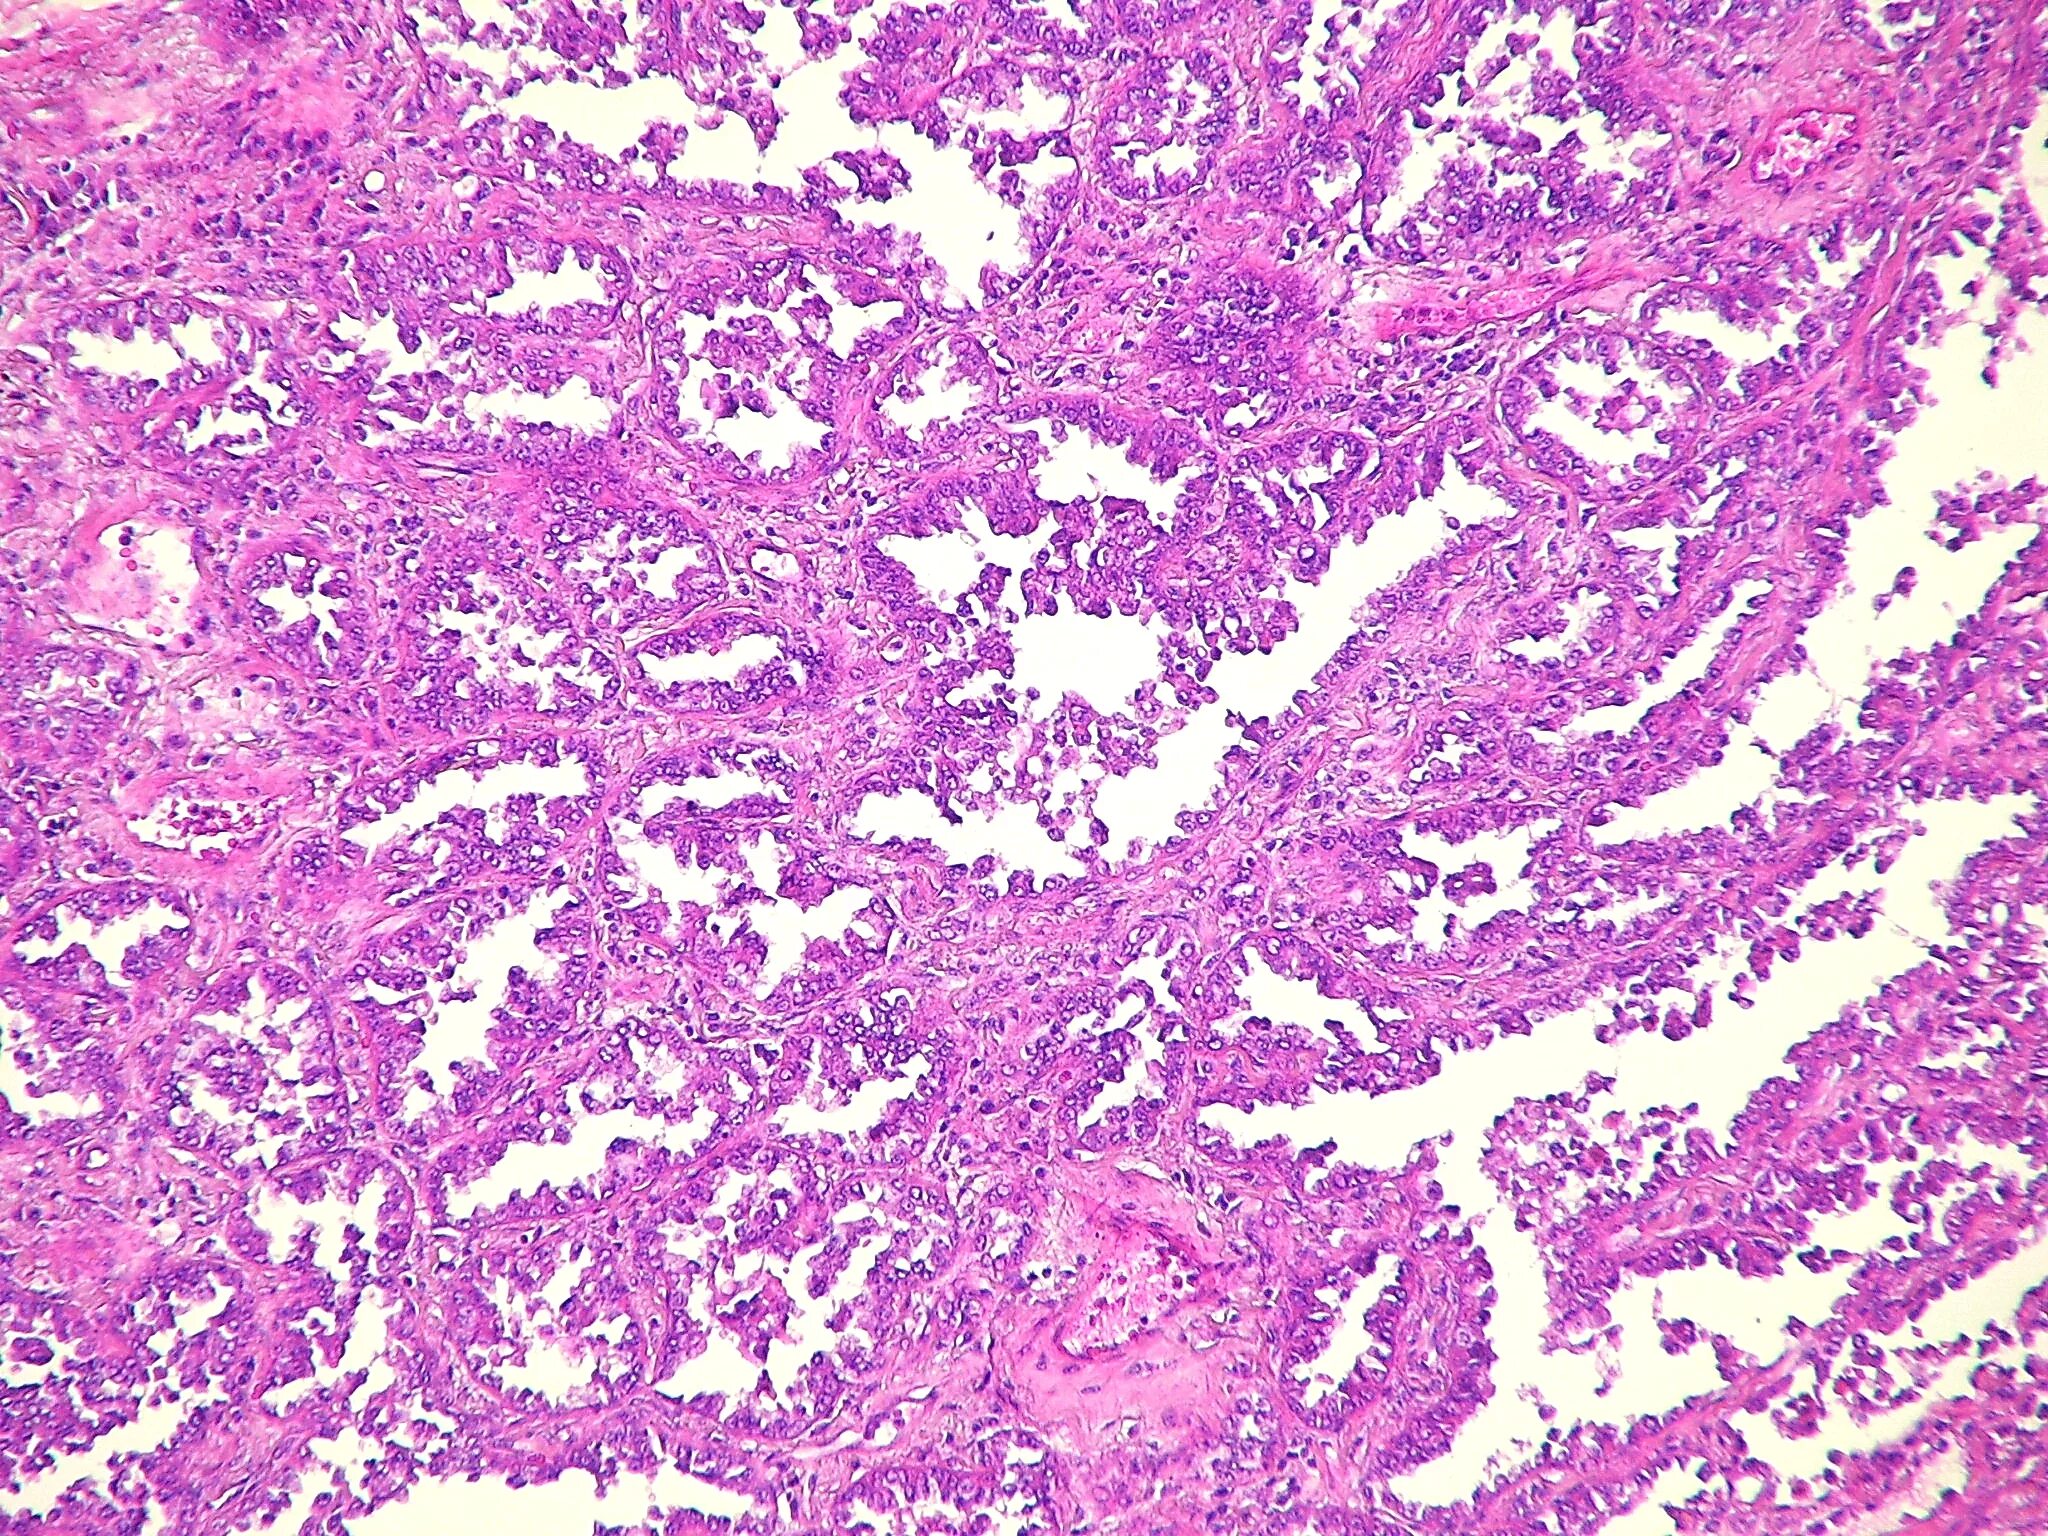

Рак легкого гистологические